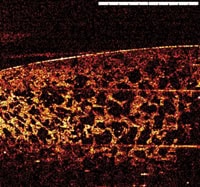

To demonstrate the potential of Multi-Beam OCT for monitoring the progression of wound healing, an OCT image of skin on the back of the author's hand was taken using a Michelson Diagnostics' EX1301 OCT Microscope. This image is shown in Figures 2 and 3. The progress of the wound healing process is visible, including scab formation and gradual expulsion of the scab as the epidermis re-grows underneath.

| Figure 3: A series of five images taken over four days showing formation of scabs and re-growth of epidermis. Image size 5mm X 2mm approx |

| Figure 4: Tissue scaffold (image courtesy of University of Edinburgh) | Figure 5: Multi-Beam OCT image of a section of skin, approx 5mm by 1.4mm with a resolution <10μm |